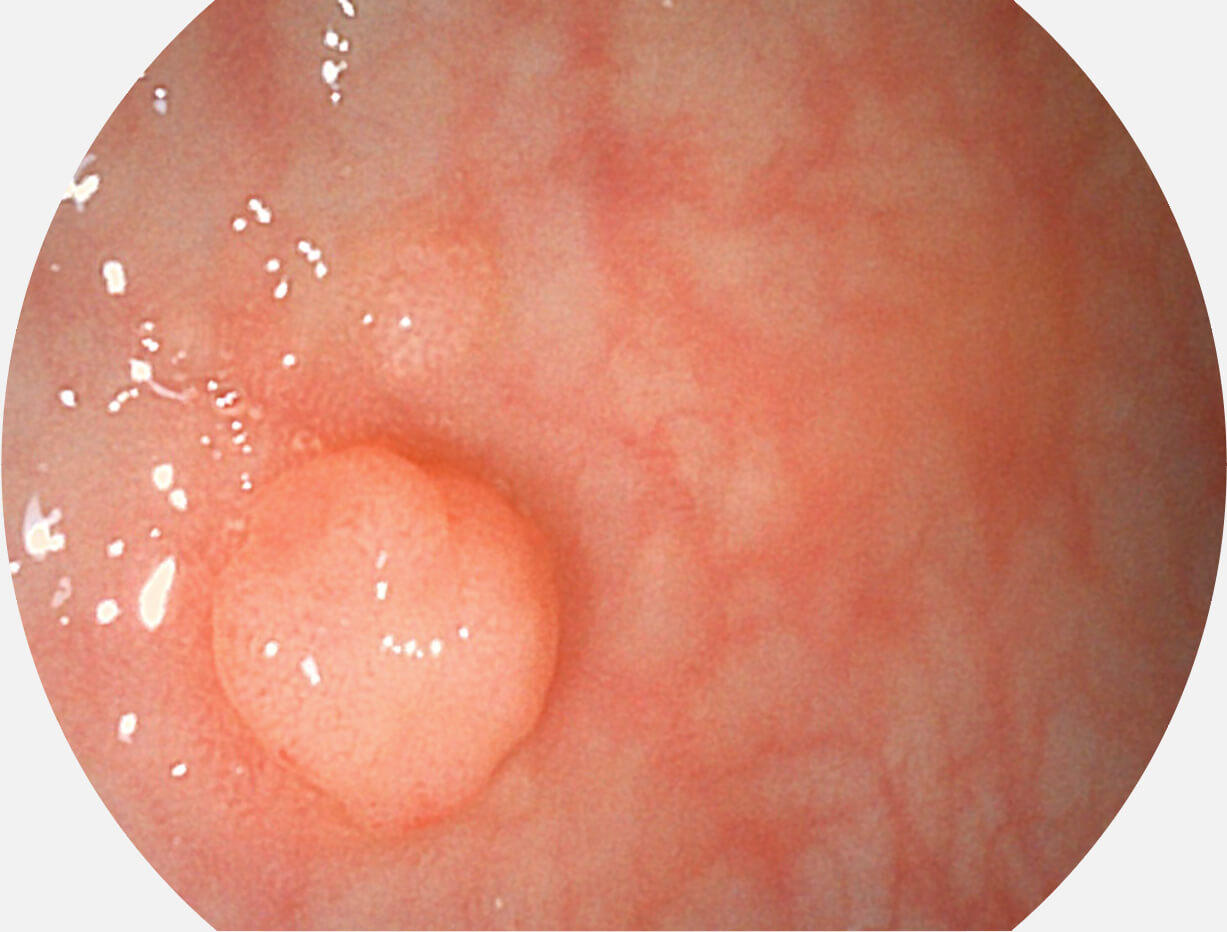

白光图像

VIST图像

Versatile Intelligent Staining Technology, VIST

强调浅层黏膜结构的同时,保证照明亮度和提升浅层微血管与中层血管颜色对比度,病变边界更清晰。

采用光路合束技术,光谱自由度高,实现了更丰富的照明模式,染色模式SFI及VIST,从远景到近景,助力消化道早期疾病诊断。